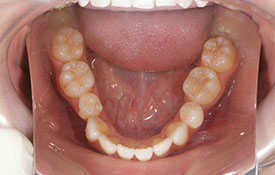

インビザラインの治療例:CASE-1

| プロフィール | 42歳 女性 |

| 所見 | 他院で行われた矯正歯科治療後の後戻りに悩まれて来院されました。 アイライナーの装着は、1日平均20時間ほどでした。 |